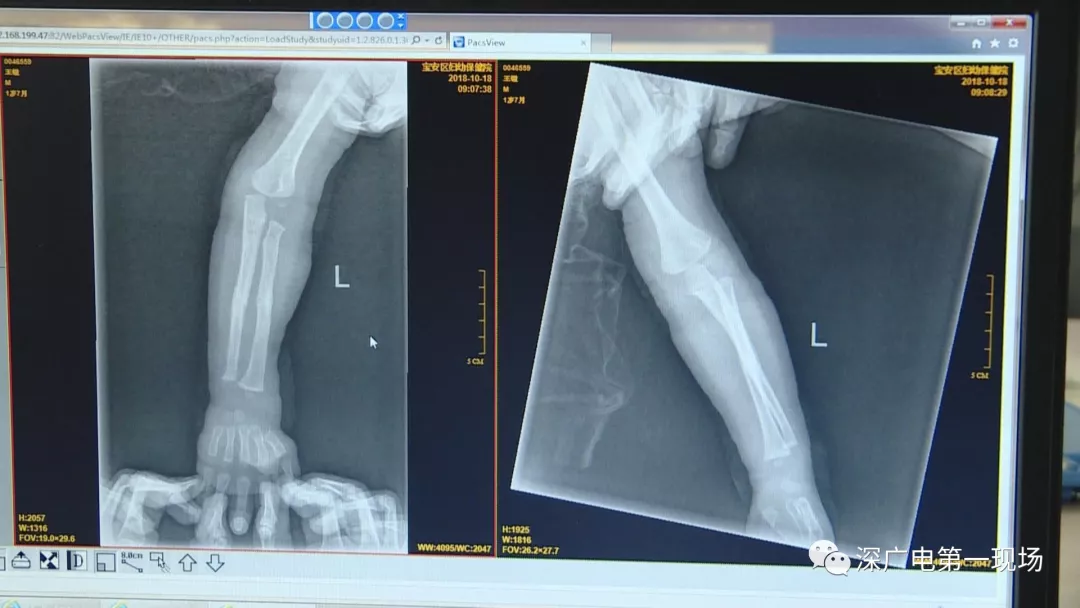

9月4號,一名1歲零5個月的男嬰因在家中摔傷,被父母送到了寶安區(qū)婦幼保健院,醫(yī)生診斷為左側尺橈骨骨折。在進行全麻手術之前,院方例行對嬰兒進行了周身檢查。手術前,兒外科醫(yī)生趙冠聰在查看患者的胸片時,發(fā)現(xiàn)這名嬰兒的胃部有一枚硬幣大小的暗影。